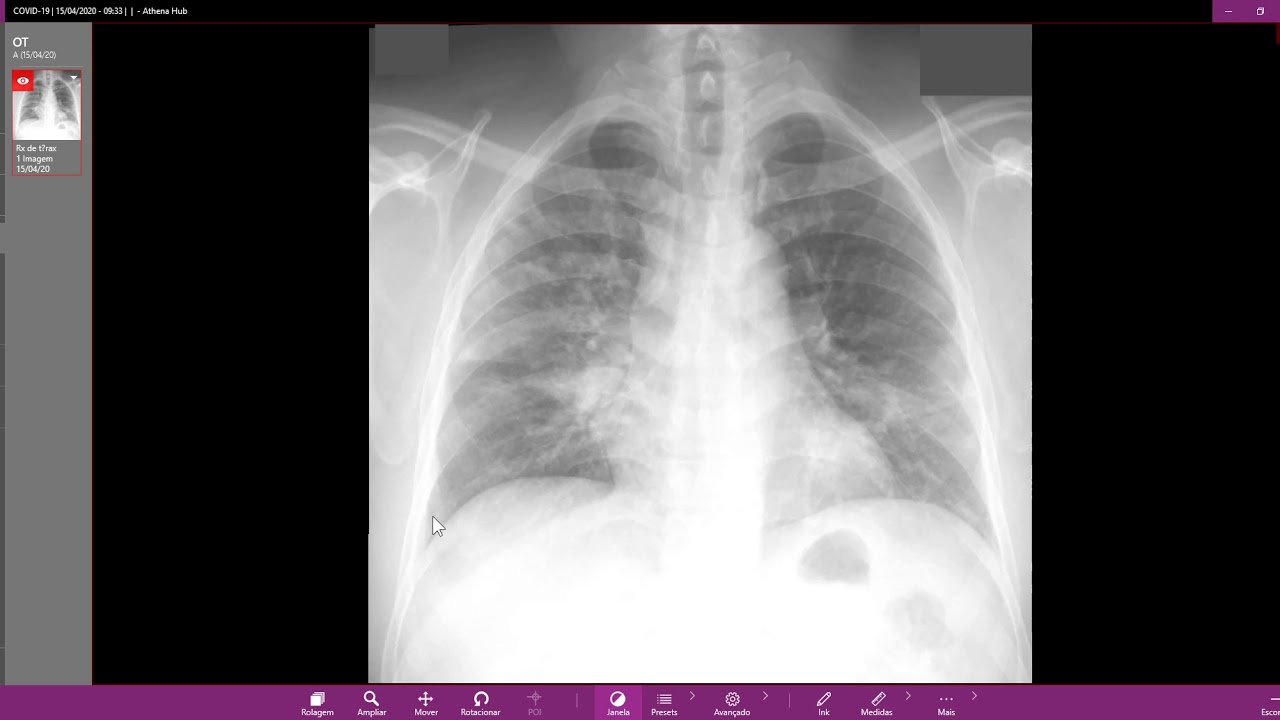

Rx de tórax COVID 19 - YouTube

Pneumonias Virais e COVID-19: Aspectos em Imagem do Tórax › Artigos | Fleury Medicina e Saúde